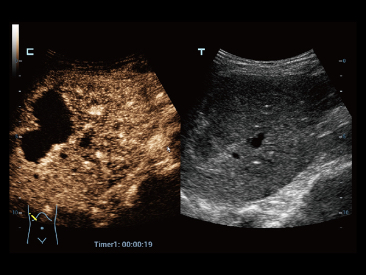

Desde que se fund├│ la compa?├Ła, Mindray ha explorado incansablemente nuevas formas de mejorar la confiabilidad del diagn├│stico. Con la revolucionaria tecnolog├Ła de ZONE Sonography?, la nueva plataforma ZST+ de Resona?7 lleva la calidad de la imagen por ecograf├Ła a un nivel superior mediante el procesamiento de datos de canal y la adquisici├│n de zona.

Adem├Īs de la calidad de imagen de primer nivel, Resona?7 tambi├®n mejora las capacidades de investigaci├│n cl├Łnica con el revolucionario V?Flow para la evaluaci├│n hemodin├Īmica vascular y con la adquisici├│n de planos m├Īs inteligente a partir de conjuntos de datos 3D para el diagn├│stico del SNC fetal. Al combinar el funcionamiento multit├Īctil basado en gestos m├Īs intuitivo y todas las caracter├Łsticas cl├Łnicas esenciales, Resona?7 realmente lidera las novedades en innovaci├│n de ecograf├Łas.